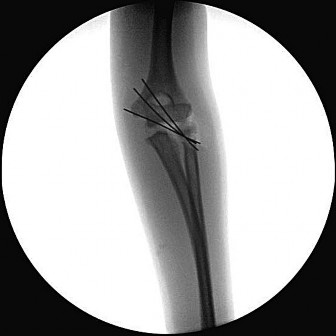

Question 42:

A 45-year-old male sustains the injury pattern depicted in the provided image. During surgical reconstruction of the lateral collateral ligament complex, identifying the correct isometric origin of the lateral ulnar collateral ligament (LUCL) on the distal humerus is critical. Where is this point located?

Correct Answer: At the center of the axis of rotation of the capitellum

Explanation:

The isometric point for the LUCL origin on the humerus is the center of the axis of rotation of the capitellum. Placing a graft or suture anchor at this specific geometric location ensures that the reconstructed ligament maintains relatively constant tension throughout the elbow's entire arc of flexion and extension.